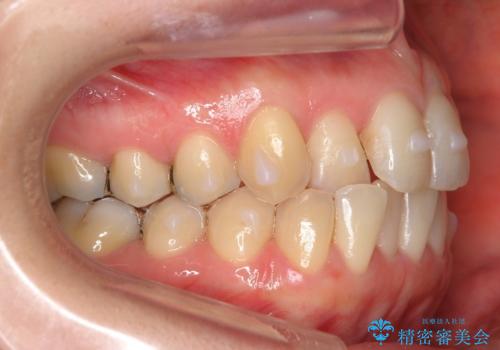

上の前歯が一部引っ込んでいる 下のがたがた マウスピース矯正

- 前歯2本が後ろに引っ込んでいる状態でした。

マウスピースで歯を抜かずに矯正しました。

かみしめがある方は、奥歯のかみ合わせが弱くなることがマウスピース矯正の欠点ですが、装着時間や時間帯を工夫して奥歯もしっかりかんだ状態で矯正終了をしています。

かみしめがある方には、単にマウスピースをお渡しするだけでなく、奥歯のかみ合わせまで面倒を診る、引き出しの多い歯科医に見てもらうのがおすすめです。奥のかみ合わせが弱くなっても、患者さんにはなかなかわかりにくいです。